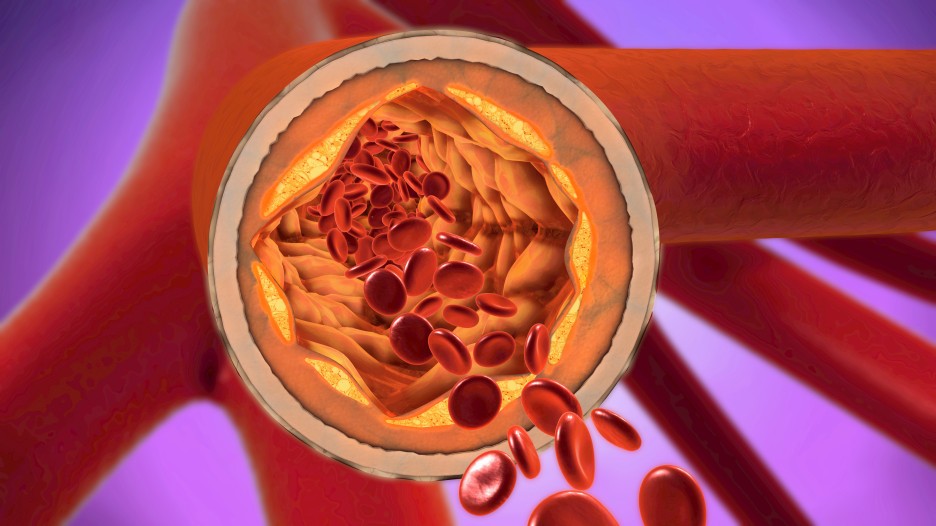

이처럼 지질이상증은 홀통혈관이 막힐 때까지 증상이 나타나지 않기 때문에

흐림이 막혀 동맥경화를 유발하고

심장 및 혈관질환을 일으킬 수 있습니다.

특히 고지혈증으로 인한 동맥경화는 혈관 내막에 노폐물이 쌓여 혈관 내경이 좁아져 혈류장애를 유발할 수 있습니다.

또한 동맥경화의 경우 특별한 증상이 나타나지 않으므로

동맥의 약 70% 이상이 막혔을 때 가끔 목덜미가 짜릿하거나 손이 떨리는 증상이 나오기도 합니다.

만약에 혈관이 심해져서 막히면

심근 경색이나 말초 동맥 질환 등의 합병증으로 이어질 수 있습니다.